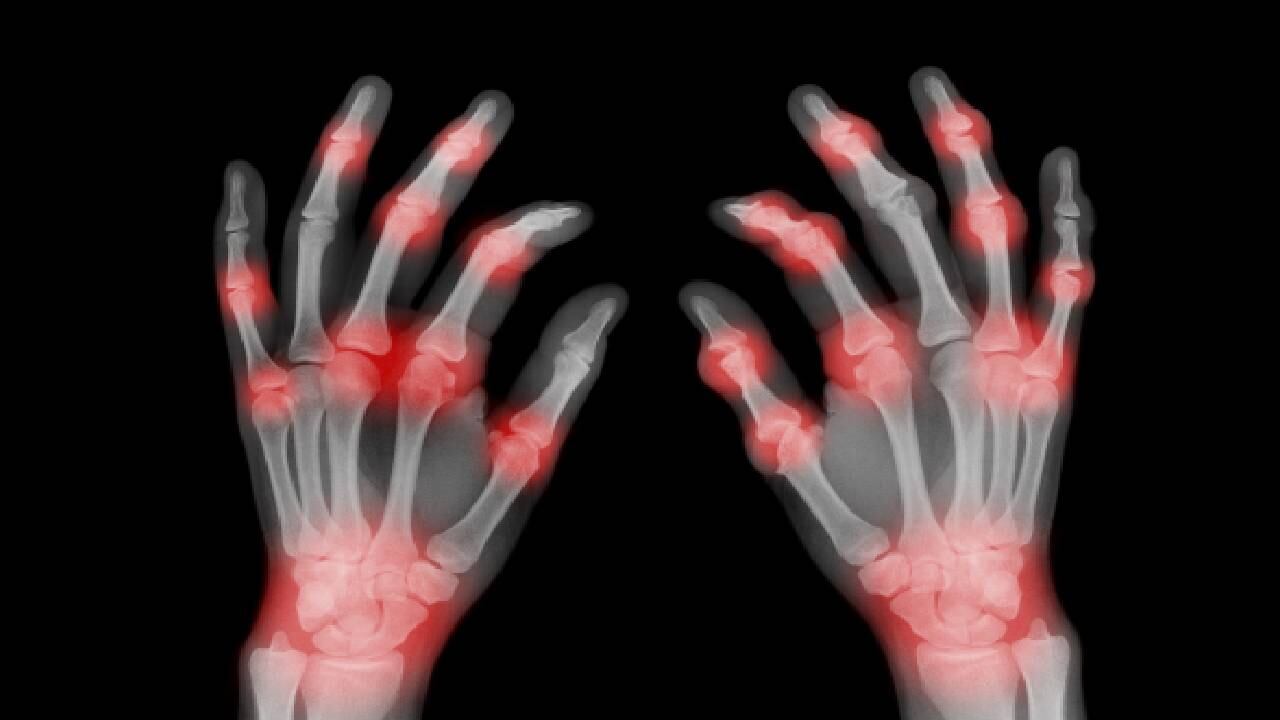

En Colombia existen diversas enfermedades, algunas desconocidas, que afectan la calidad de vida de los colombianos, dentro de estas patologías se destacan la artrosis, artritis, hernias discales, sindrome de manguito rotador, tendinitis y bursitis. Estas patologías pueden generar molestias, incluso discapacidades para desarrollar las actividades del día a día, asimismo, el desconocimiento de las mismas, influye en un diagnóstico tardío que puede perjudicar la salud de las personas.

De acuerdo con la Revista Colombiana de Reumatología, de un total de 6.693 personas encuestadas, el 64 % fueron mujeres que aseguraron presentar dolores frecuentes en rodillas (35 %), manos (26 %), columna lumbar (20 %) y hombros (16 %); de igual manera, la artritis y la lumbalgia crónica fueron las condiciones inflamatorias más comunes.

Por otro lado, existen varias enfermedades como: artrosis de rodilla, metatarsalgia, artrosis de cadera o artrosis coxofemoral, artrosis de tobillo, condromalacia rotuliana, osteocondrosis de Freiberg, artritis reumatoide de tobillo y pie o poliartritis, que se pueden tratar con ácido hialurónico infiltrado, como tratamiento alternativo que ofrece un alivio paulatino del dolor y una mejora general de las funciones del cartílago lesionado. Vale la pena advertir que el efecto de estos tratamientos no suele ser inmediato sino a medio y largo plazo.